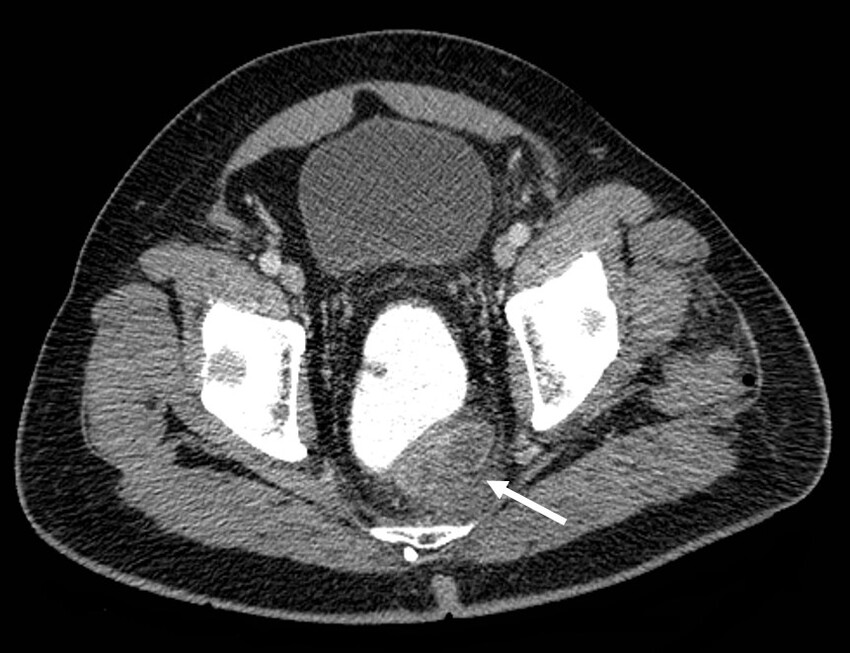

Además, se identificó trombosis de la vena mesentérica inferior y sus afluentes, la vena cólica izquierda y vena rectal superior, con marcado aumento en su calibre, engrosamiento e irregularidad de sus paredes, además de estriación de la grasa circundante, hallazgos compatibles con tromboflebitis (Figs. 2, 3 y 4).